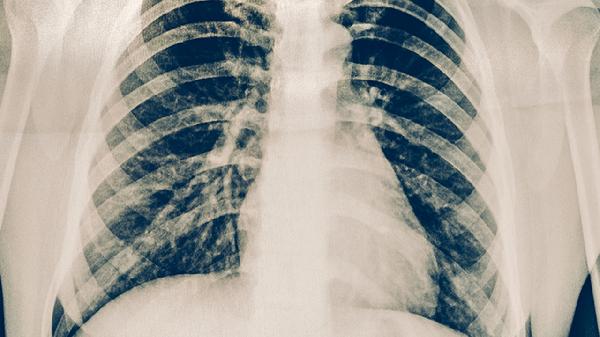

胸肋软骨炎的症状主要有局部疼痛、压痛明显、肿胀隆起。胸肋软骨炎是发生在胸骨与肋骨交界处软骨的炎症反应,多与外伤、慢性劳损或病毒感染有关。